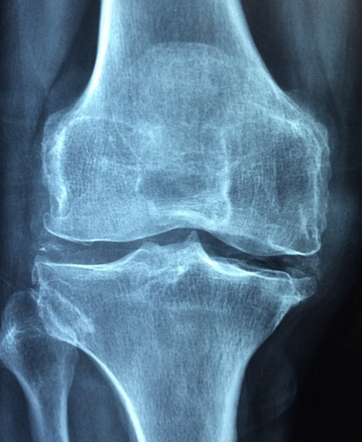

무릎은 하지의 대표적인 관절 중 하나로, 허벅지뼈와 종아리뼈, 그리고 무릎뼈가 연결되어 있는 부분입니다. 무릎은 우리가 걷거나 달리는 등 하지를 사용할 때 매우 중요한 역할을 합니다. 또한, 무릎은 축적된 에너지를 해방시키는 역할도 하며, 다양한 각도에서 움직이는 구조를 갖고 있습니다. 하지만 무릎은 매우 복잡한 구조이기 때문에 과부하나 부상, 연령에 따른 변화 등으로 인해 문제가 생길 수 있습니다. 무릎이 안 좋아지면 걷기 어려움을 비롯한 여러 가지 문제가 발생할 수 있기 때문에, 무릎 건강을 유지하기 위해 적절한 운동과 균형 잡힌 식습관을 유지하는 것이 중요합니다.

- 퇴행성 관절염: 무릎 관절에 있는 연골이 닳아서 뼈와 뼈가 마찰하면서 통증이 생기는 질환입니다. 나이가 들면서 자연스럽게 발생할 수 있으며, 과체중이나 관절에 부담을 주는 운동 등이 위험 요인입니다.